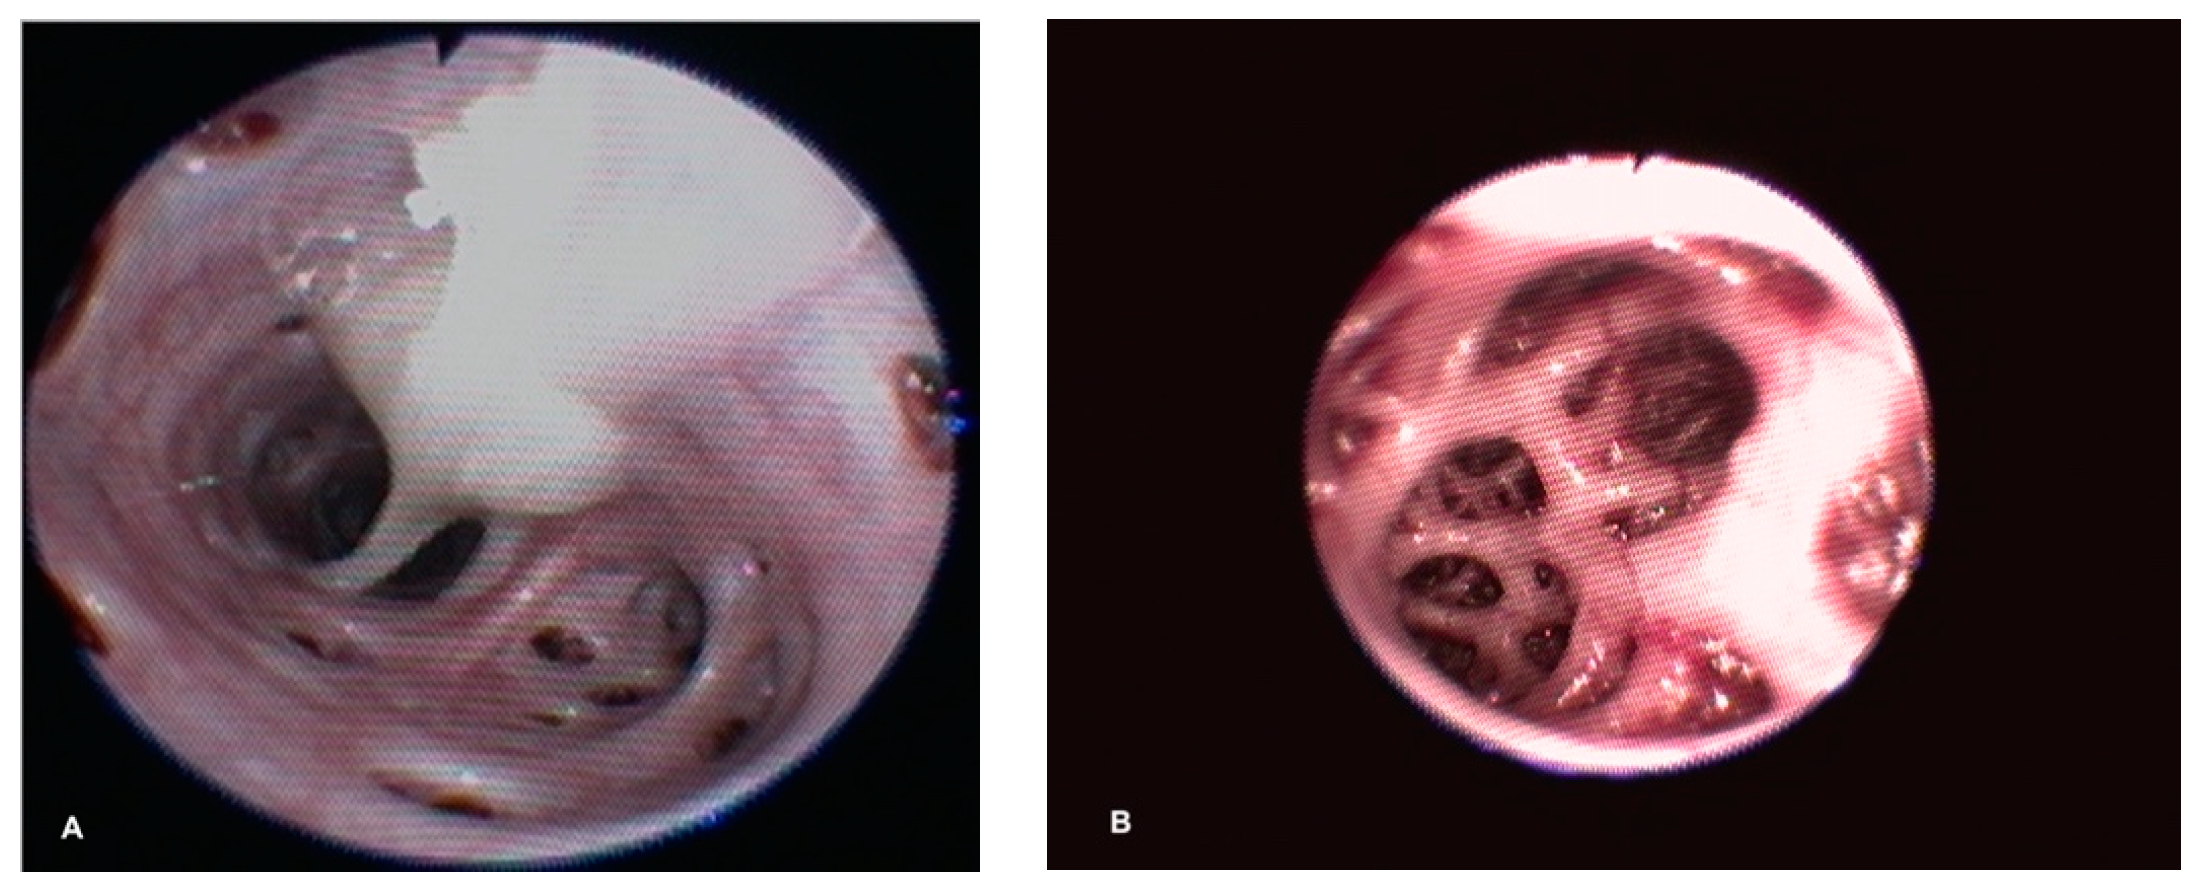

Upon radiographic examination, four of the turtles exhibited severe pneumocoelom. Radiographic signs of pulmonary pathology were seen in all cases; 4 unilateral and 10 bilateral. In these turtles, an increased pulmonary radiopacity, with areas of inhomogeneous parenchyma, interstitial pattern and/or alteration of the pulmonary profile, was found (Figure 1). In one turtle, the radiographic examination showed a reduction of the right lung volume.

Figure 1. Dorso-ventral DV (A), Latero-lateral LL (B) and Craniocaudal CrCd (C) radiographic projection of a Loggerhead sea turtle: bilateral areas of increased pulmonary radiopacity with a reticular pattern (honeycomb) and accentuation of the intrapulmonary bronchi that suggest pulmonary disease.